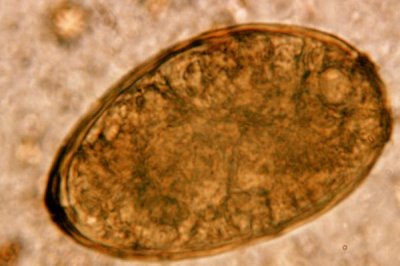

1、肺吸虫

肺吸虫亦称卫氏并殖吸虫,第一中间宿主是川卷螺,第二中间宿主有溪蟹、喇蛄等,人因食生小龙虾或未煮熟小龙虾易感染并引发肺吸虫病。

2、肝吸虫

肝吸虫亦称华支睾吸虫,第一中间宿主是中小型螺类,第二中间宿主有鱼类、虾类、蟹类等,成虫可寄生于人体肝、胆管内并引发肝吸虫病。

3、裂头蚴

裂头蚴学名曼氏迭宫绦虫,第一中间宿主是剑水蚤.第二中间宿主有蛙、蛇、鸟、猪、虾等,人可作第二中间宿主、转续宿主甚至终末宿主。